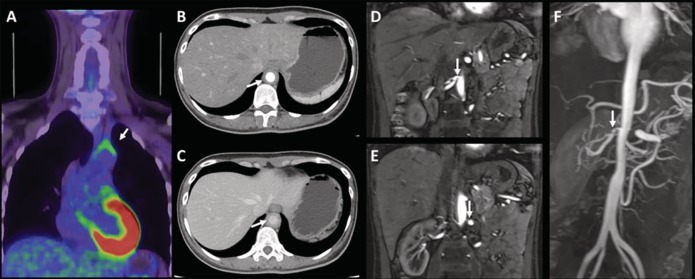

Asymptomatic hypertension and bilateral renal artery stenosis in Takayasu arteritis.